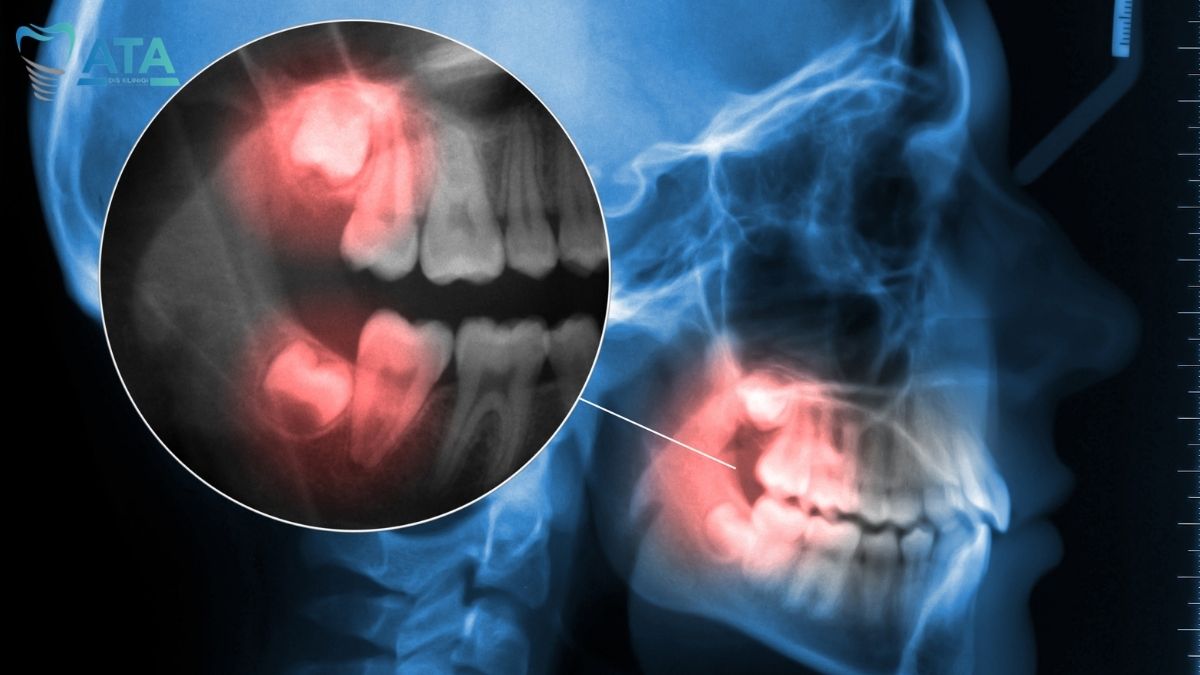

Diş çekimi öncesinde, hastaya kapsamlı bir ağız içi muayene uygulanır ve gerekli görülen durumlarda radyografik (röntgen) görüntüleme yapılır. Dişin pozisyonu, kök şekli ve çevre anatomik yapılar alanında uzman hekim tarafından ayrıntılı şekilde değerlendirilir. Muayene sonucunda, hastaya planlanan diş çekimi prosedürü hakkında bilgilendirme sağlanır. Gömülü diş gibi cerrahi müdahale gerektiren durumlarda ise, ilgili cerrahi planlama titizlikle oluşturulur.

20’lik Diş Cerrahi Çekim

Gömülü veya kırık dişlerde cerrahi çekim uygulanır. Lokal anestezi altında steril koşullar altında gömülü diş çekimi yapılır. Yöntem, komplikasyon riskini en aza indirir.